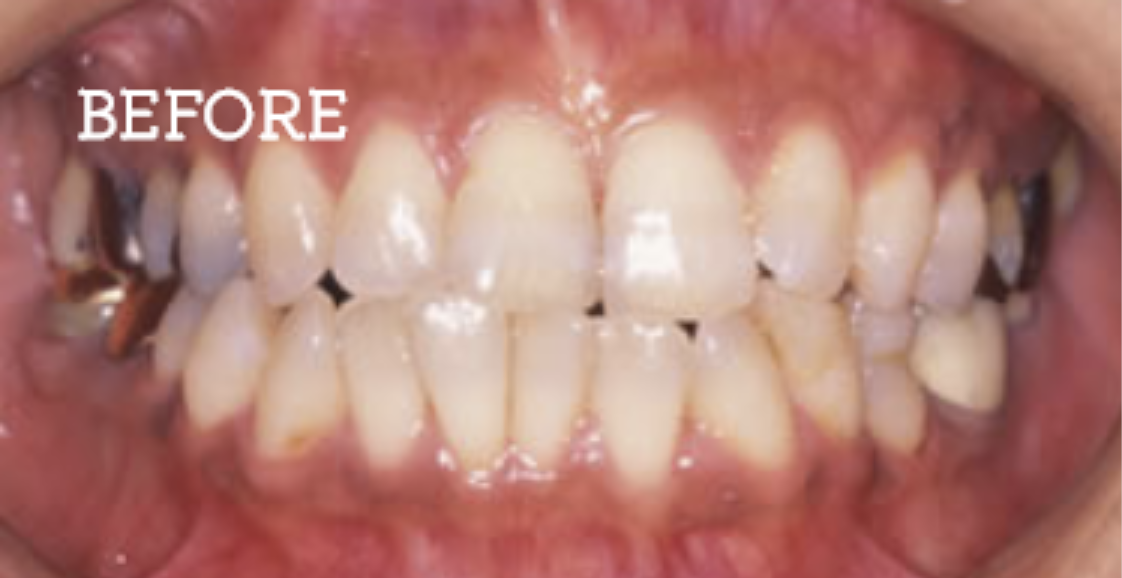

20年以上も持続する治療効果の実現

当院では一時しのぎではなく根本的な治療を行うことで、治療効果の持続性を実感できます。

定期的なメンテナンス調整は必要ですが、実際の症例として、治療後20年以上も改善された口腔を維持されている患者様もおります。

自由診療での治療の場合、費用は決して小さい額とは言えませんが、その費用対効果は保証いたします。